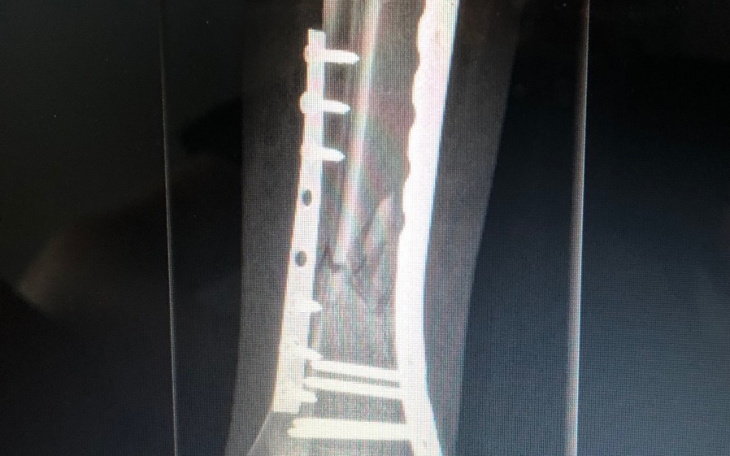

23 Maja uległam wypadkowi zdiagnozowano wieloodłamowe złamanie 1/3 dalszej trzonów kości strzałkowej oraz piszczelowej prawej. Niestety do tej pory nie ma zrostu muszę poruszać się o kulach. Prowadzona rehabilitacja nie przynosi efektów. Pewną szansą jest leczenie za pomocą ultradźwięków urządzeniem Exogen jest to kosztowna metoda niestety nie jest refundowana przez NFZ a moje oszczędności pochłonęło dotychczasowe leczenie